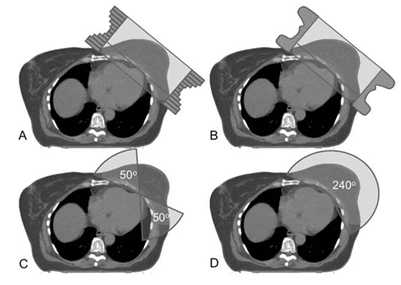

KUH has found that tVMAT (see figure 1) effectively achieves homogeneous dose coverage for WBI, with reduced dose to the heart and ipsilateral lung and no increase in dose to the contralateral breast or lung1.